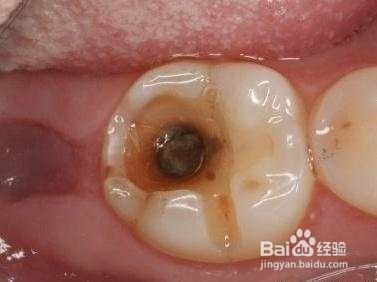

龋齿。糖尿病患者患病后唾液大幅减少,不能很好的清洁口腔,加上唾液的酸度上升,很容易造成龋菌的滋生。